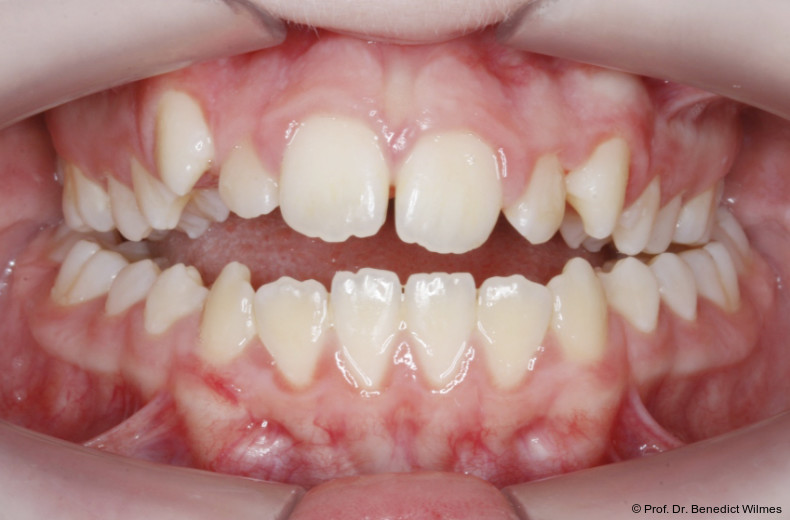

Eine 13-jährige Patientin stellte sich mit beidseitigem Kreuzbiss, einem anterioren offenen Biss und einer Angle Klasse II vor. Das viszerale Schluckmuster wurde mittels logopädischer Maßnahmen umgestellt, der offene Biss persistierte jedoch (Abb. 3a–l).

Als alternative Therapie wurde die chirurgische Korrektur des offenen Bisses nach Abschluss des Wachstums vorgeschlagen. Eltern und Patientin entschieden sich allerdings für die non­chirurgische und weniger invasive Molarenintrusion.